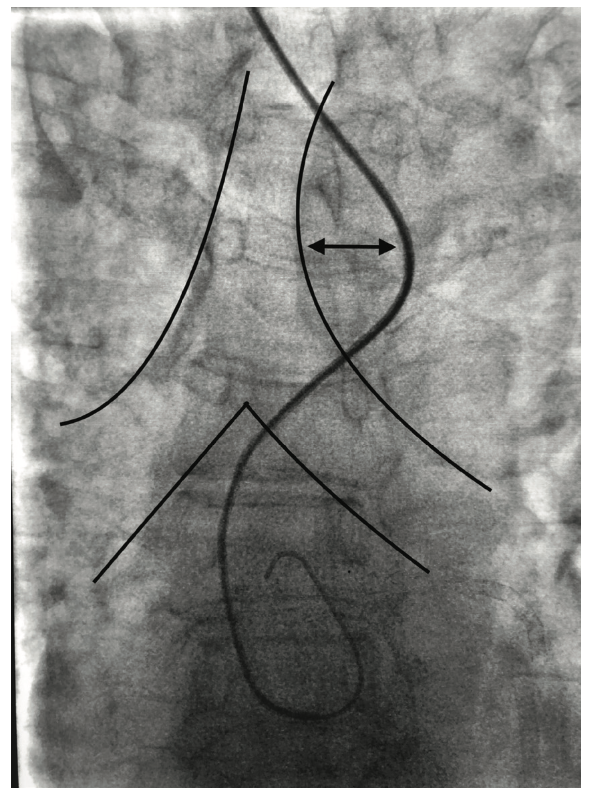

Radiographically, all have a similar appearance (Figures 5-8). They move left across the trachea, well into the lung field, and make an acute trajectory change back to the right, towards the transverse and ascending aorta. This abrupt course of the catheter change resembles a “shark’s tooth” and as a radiographic sign, may offer the clue of an aberrant subclavian. Different wires may enable easier negotiation into the ascending aorta. Wholey wires (Medtronic) may be used because of their soft tip and strong shaft. Hydrophilic wires such as Glidewires (Terumo) are also used to navigate through the aberrancy. Keeping an Amplatz super stiff wire in the catheter may help provide the necessary support for selective coronary angiography. Even if operators get close to the coronary ostia, tension and energy built up in the catheter can disallow selective engagement and force a bailout to the contralateral radial or the femoral approach. Conversely, there are times in the presence of this ominous anatomy when catheters will engage quicker than the operator can do a “time out.” A skillful operator might display some “catheter legerdemain” to negotiate these problems; however, a little bit of luck also goes a long way. One doesn’t necessarily have to be a funambulist to recognize and selectively cannulate the coronaries.

With “standard” right subclavian tortuosity, the catheter crosses the right to left side of the trachea and has a rounded out shape (Figure 2B). Catheters also move inferiorly for a few centimeters before moving back right towards the trachea again, prior to reaching the sinotubular junction. In contrast, with an aberrancy, the catheter crosses the trachea and travels significantly left past the trachea and abruptly turns back to the right, towards the transverse and ascending aorta that is delineated quite well with an left anterior oblique (LAO)/caudal view. The catheter may also follow a superior trajectory before reaching and/or cannulating the coronary ostia (Figure 3).